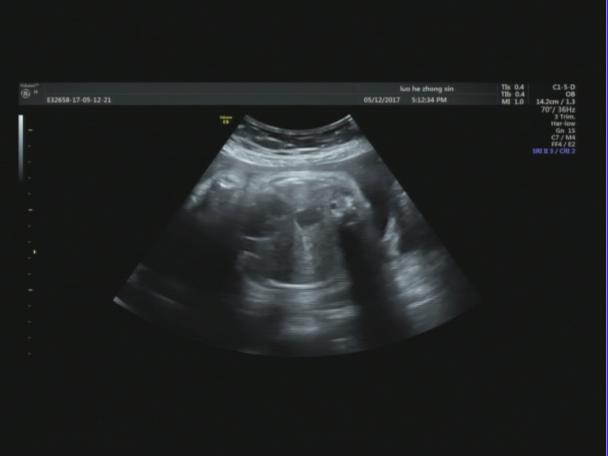

【声像图表现】 胎儿心脏:四腔心切面可显示,左心偏小,右心偏大.主动脉内径明显偏细,PA:7.1mm,PAV:84cm/s,AO:4.0mm,AOV:38cm/s,因体位限制,主动脉弓显示不清。胎儿腹部内脏:胆囊位于腹腔左侧,心脏及胃泡位于右侧胸腔,心房反位,心室左襻,肺动脉发自功能右室,主动脉发自功能左室,三尖瓣增厚,回声增强,四腔心切面可显示.左心明显偏小,右心明显扩大。因胎儿体积大位置较远,左房明显小,未探及明显的肺静脉血流信号入左房。

32周的孕妇,这次超声检查是发现胎儿肝脏,胆囊位于腹腔左侧,心脏及胃泡位于右侧胸腹腔,理论上胎儿肝脏、胆囊应位于腹腔右侧,胃泡位于腹腔左侧,心脏位于胸腔偏左侧,但是这个胎儿不仅存在着脏器反位,而且从声像图来看胃泡和心脏位于一个切面,难以分清是在胸腔还是腹腔。根据超声资料,胎儿心脏还表现左心偏小,右心偏大.主动脉内径明显偏细,因体位限制,主动脉弓显示不清。因胎儿体积大位置较远,左房明显小,未探及明显的肺静脉血流信号入左房,说明胎儿心脏也存在发育不良。

正常膈肌的超声声像图表现为:紧贴肺及心脏下缘、肝脏上缘的薄带状低回声,位于胸腹腔之间,明显向胸腔突出的圆顶状结构。但是在这个患者的声像图里我们并没有找到这样的结构,后来患者去了上级医院复查,也证实了我们的诊断:胃泡位于胸腔(考虑膈疝);右位心。一般来说膈疝是膈的发育缺陷导致腹腔内容物疝入胸腔,膈疝特征性超声声像图包括:腹围较正常偏小,胸腔内出现移位的胃泡、有蠕动的囊性结构、存在血供来自肝脏实性占位等,心脏轴线偏移,无膈肌超声声像图等。当发现心脏轴线移位时要注意排除胸内致病因素,需注意与肺囊腺瘤、肺囊肿、肺肿瘤、隔离肺、支气管囊肿、一侧胸腔积液、膈膨升等鉴别。与膈疝最容易混淆的是先天性肺囊腺瘤畸形,先天性肺囊腺瘤畸形的囊腔大小相对稳定,短时间内不会有变化,而膈疝的胃肠结构在短时间内会有蠕动,会有变化。另外还应特别注意膈膨升,膈膨升于矢状切面上能观察到膈肌呈弧形低回声分隔胸腹腔,但膈肌水平明显高于肋弓水平。

是较少见的先天畸形之一,由于膈肌的发育缺陷导致腹腔内容物疝入胸腔,发病率约为新生儿的1:2000-1:3000,约占所有产前检出胎儿畸形的3%。膈疝胎儿生后死 亡 率 可 高 达 60%,若合并其他畸形,则 死 亡 率 可 高 达 79%。国外大宗报道膈疝的产前诊断率约 59%,不同地 域之间差距较大(30%-75%)。超声可显示胎儿膈肌,正常膈肌表现为圆顶突向胸腔的薄带状低回声结构,位于胸腔与腹腔之间,紧贴肺与心脏的下面,肝脏上面,在胎儿矢状及冠状切面显示最清楚,但超声评价整个膈肌的完整性较困难,通常只有当腹腔内脏器进入胸腔内,才可能被检出膈疝典型的胎儿先天性膈疝声像图表现为正常胎儿左、右肺环绕四腔心切面特征消失,胸腔内发现占位病变。文献报道先天性膈疝以左侧多见,病变多为 混 合 性 回 声,其中胃泡回声最具有特征性,近 50%合并其他异常,其中心血管系统畸形最为常见,像这个患者就是膈疝合并左心发育不良。产妇在产前进行超声检查可有效诊断出胎儿是否具有先天性膈疝及其合并畸形,但同时,超声检查并不能检测出膈肌的缺损部位,若没有出现腹腔内脏器穿过膈肌的现象时,无法检测出膈肌的缺损程度。外院的漏诊也同样是给我们敲响了一个警钟,因此我们在进行产前超声诊断的一定按顺序,认真仔细,不遗漏我们看到的每一个部位,这既是对患者负责,也是对我们自己负责。